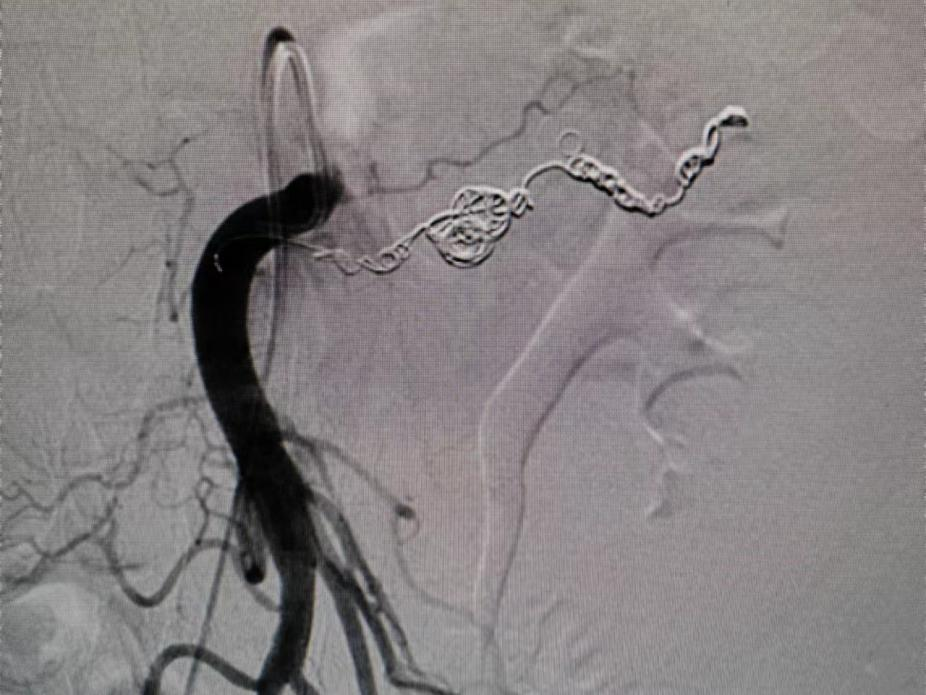

术前CT

在CT引导下术中精准造影

很快就找到了出血点

原来是肠系膜上的假性动脉瘤破裂

迅速对出血点进行栓塞

出血终于止住了!

据术中估算

赵大伯的腹腔内约有接近

3000mL的出血量